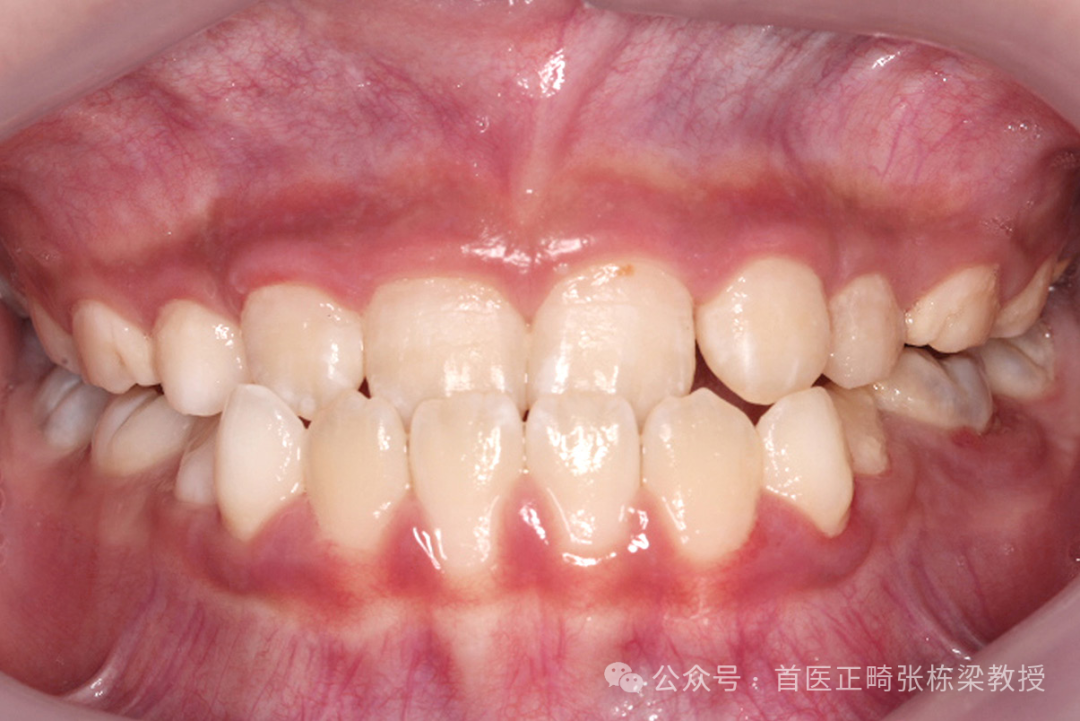

说到儿童地包天,这也是儿童乳牙列常见的牙齿问题,它是指儿童的下颌骨发育过度,导致下牙咬合在上牙的前面,形成一种“地包天”的外观。

对于儿童地包天早期矫正,不是看到就贸然戴牙套操作,我们也需要做好鉴别,到底是牙齿的问题还是骨骼的问题?

当然5岁以下的乳牙列孩子出现地包天 ,通常不是真正意义上的骨性地包天,极少数的孩子的确是由于上颌骨发育不足造成的地包天,临床中绝大多数来找我做早期矫正的孩子都是由于肌功能问题导致的下颌骨位置前移。

我们针对不同的地包天各有合适的方法,区别点就是要鉴别孩子的地包天是牙齿的问题还是骨骼的问题。

那事实上临床中我所遇到的这些病例中,绝对不是单一的原因,往往是很多复杂的原因,既有牙的问题还有骨骼的问题,那么既有牙齿很好还有牙齿比较乱,需要多因素考虑分析。